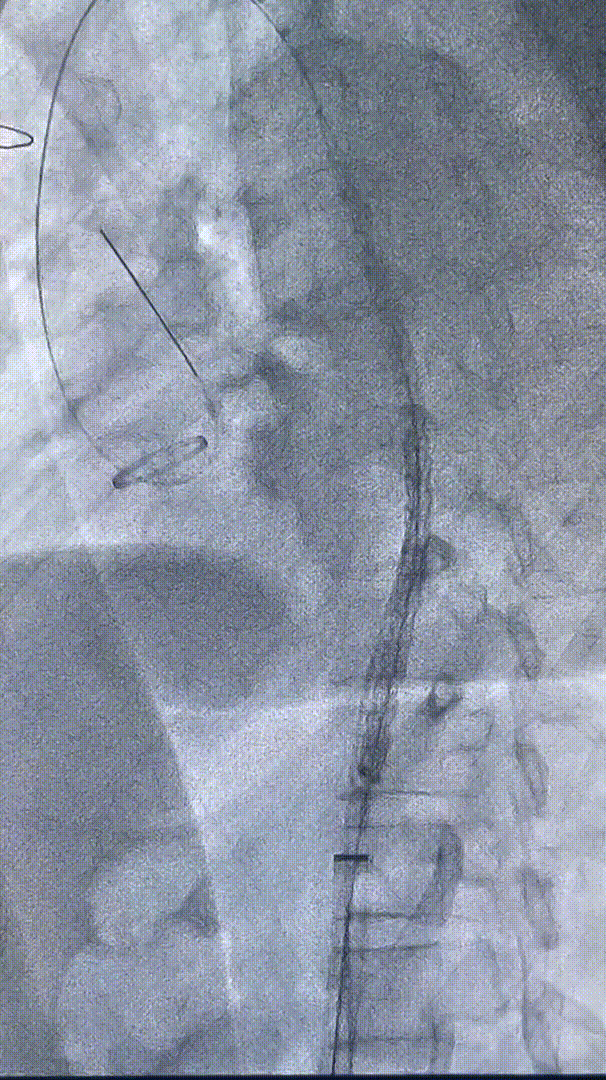

手术过程

1. 沿左侧锁骨上窝横行切开,暴露左颈总和左锁骨下动脉,行左颈总-锁骨下动脉转流(LCCA→LSA)。

2. 经右侧股动脉穿刺入路,确认导丝在真腔,行胸主动脉段造影。

gore医疗怎么样「胸有乾坤」可调可控 精准出击——四川大学华西医院肖正华教授团队:CADS治疗B型主动脉夹层病例分享_https://www.jmylbn.com_新闻资讯_第19张

术中入路造影

gore医疗怎么样「胸有乾坤」可调可控 精准出击——四川大学华西医院肖正华教授团队:CADS治疗B型主动脉夹层病例分享_https://www.jmylbn.com_新闻资讯_第20张

确认真腔